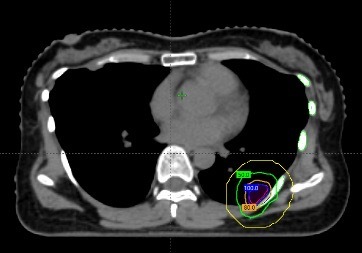

在治疗前,团队通过四维CT对三个病灶进行精准定位,尤其是紧贴肋骨的那个病灶,连与肋骨之间极其细微的间隙都被清晰标注出来。

随后进入最核心的剂量设计环节。医生与李忠伟、雷大明物理师反复推演射线路径和强度分布,把高剂量区域严格控制在肿瘤范围内,同时让剂量在极短距离内迅速下降。可以理解为,在体内完成了一次“毫米级雕刻”:肿瘤被精准覆盖,而近在咫尺的肋骨却被保护在安全范围内。